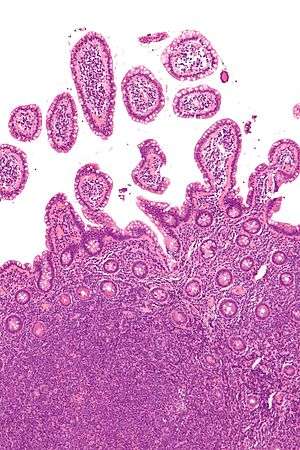

Lymphomas are types of cancer that develops from lymphocytes, a type of white blood cell.[2] Risk factors include poor immune function, autoimmune diseases, Helicobacter pylori infection, hepatitis C, obesity, and Epstein-Barr virus infection.[1][3] The World Health Organization (WHO) classifies lymphomas into five major groups, including one for Hodgkin's lymphoma.[4] Within the four groups for NHL there are over 60 specific types of lymphoma.[5][6] Diagnosis is by examination of a bone marrow or lymph node biopsy. Medical imaging is done to help with cancer staging.[1]